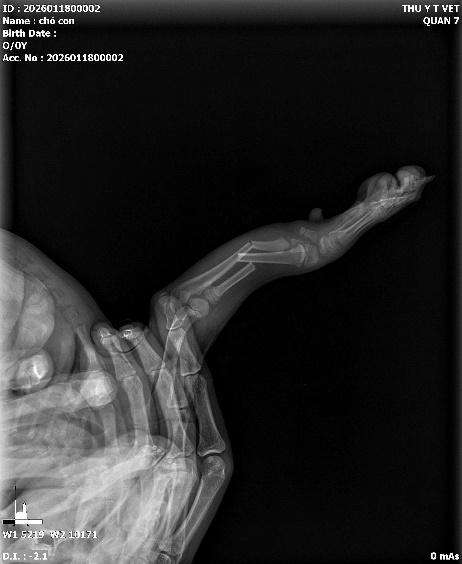

Chó mèo, đặc biệt là các bé ở độ tuổi "nhi đồng", thường có thói quen gặm nhấm mọi thứ: kim khâu, xương gà, đồ chơi cao su, hay thậm chí là vớ, kim, trang sức,..

X-quang giúp chúng tôi định vị được dị vật đang nằm ở thực quản, dạ dày hay đã xuống ruột non. Có những dị vật không cản quang (như nhựa, vải), khi đó bác sĩ sẽ cần sử dụng phương pháp chụp X-quang có cản quang (uống Barium) để theo dõi sự lưu thông của đường ruột. Phát hiện sớm dị vật giúp tránh được tình trạng hoại tử ruột, viêm phúc mạc – những biến chứng có tỉ lệ tử vong cực cao.

.jpeg)

Hình ảnh: dị vật trang sức trong ruột